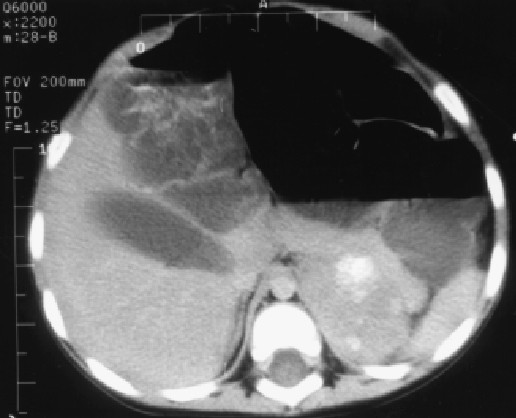

Valutazione radiologica: la tomografia computerizzata (TC) con mezzo di contrasto ha messo in evidenza una massa surrenale a sinistra con calcificazioni del diametro di 5 cm. Non altre alterazioni dei visceri, né linfoghiandolare. Una nuova valutazione della primitiva radiografia dell'addome non ha mostrato la presenza di calcificazioni.

- L'esame TC mette in evidenza le calcificazioni intralesionali molto meglio di una semplice radiografia. Forse un ECO le avrebbe potuto mettere in evidenza ugualmente.